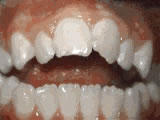

Open bite – Front teeth don’t touch

Patient sucked her thumb as a young child. She started treatment at age 13. She had braces and a special appliance — called a crib — to retrain the tongue, for 28 months. Now she can bite the lettuce out of a sandwich.